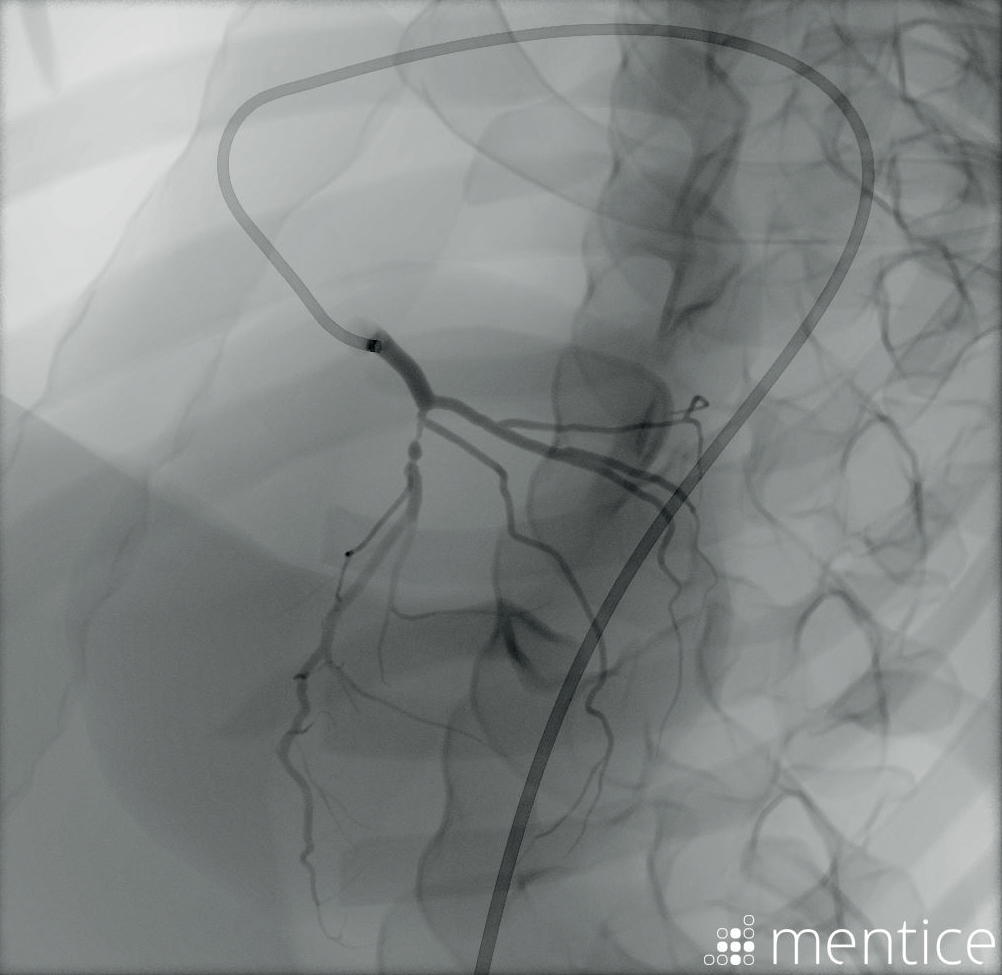

包括Mentice软件

Simman Vascular是与基于虚拟现实的介入医学模拟解决方案的世界领导者Mentice合作制造的。金宝搏188手机登录网站他们的Vist软件已集成到Laerdal的LLEAP仿真软件。

接近现实情况

通过将真实的血管内工具与监视器上的模拟图像相结合来添加现实主义。使用高级3D视频图像,Mentice软件模仿了学习者在真实荧光镜屏幕上看到的内容。